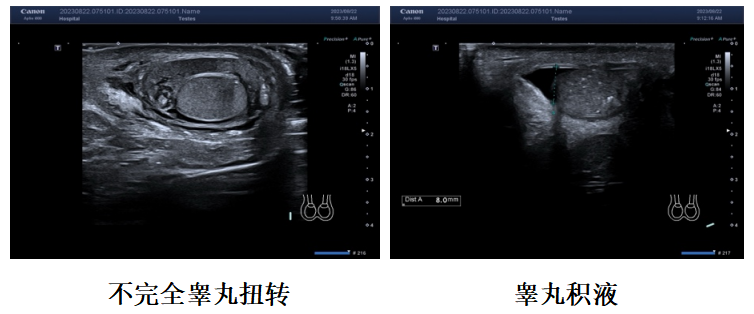

专为儿科定制的超高频、超宽频探头阵容,最高频率达24MHz,精准捕捉小儿皮下肿物、肌骨损伤、浅表组织病变等细微结构。搭载iSMI超微血流成像技术,无需造影剂即可清晰显示病灶血流:新生儿期可诊断颅脑、小肠先天性疾病;婴幼儿期助力睾丸扭转、肠套叠、肠系膜淋巴结炎紧急排查;学龄前后可监测先天性心脏病术前术后恢复,还能精准评估小儿髋关节发育、肾脏病变、神经鞘瘤等,大幅提升诊断效率与信心。